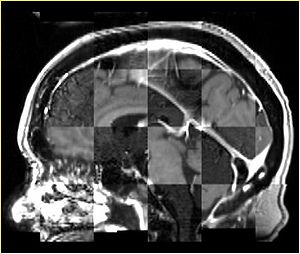

• Checkerboard appearance of unregistered images for the representative data of interest

• Case03